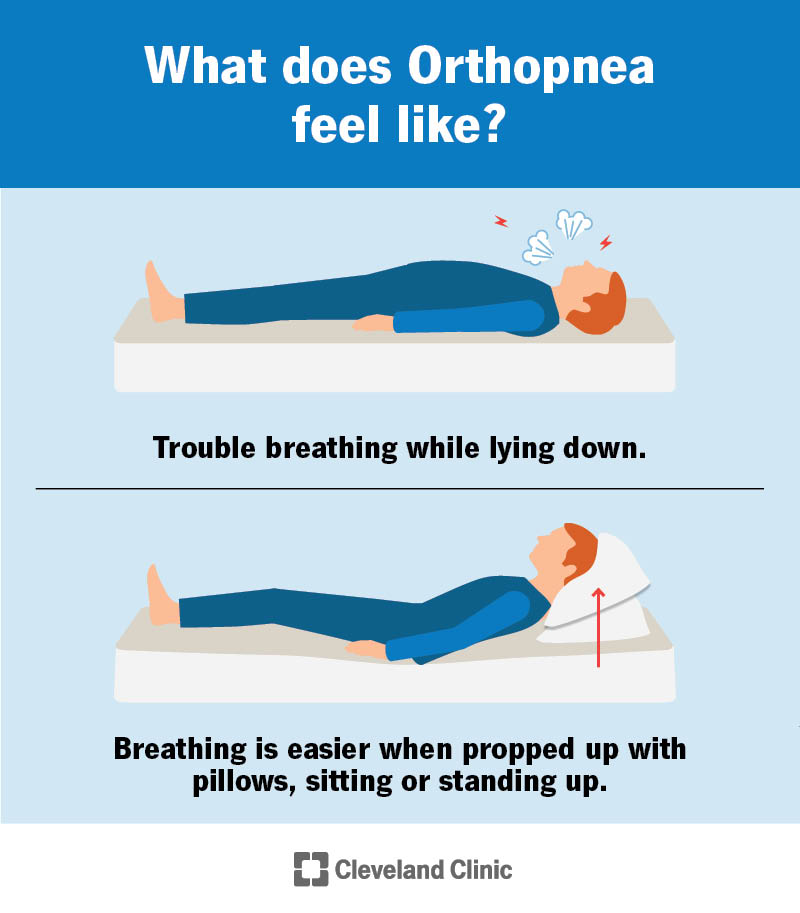

Orthopnea Causes Symptoms Diagnosis Treatment

https://my.clevelandclinic.org/-/scassets/images/org/health/articles/orthopnea